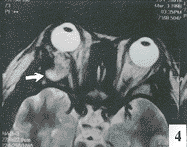

4 眼眶皮样囊肿MRI超图■